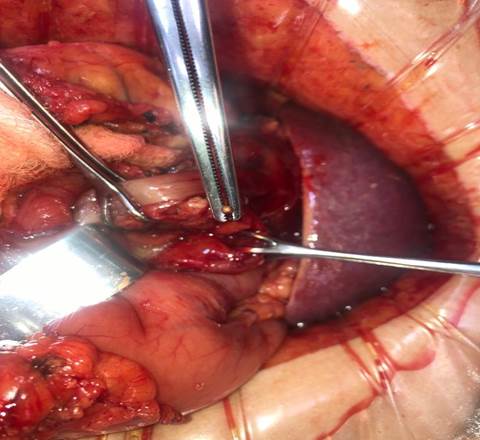

Abierto el peritoneo, no se identifica liquido intra abdominal ni citoesteatonecrosis. Se realiza la apertura de la transcavidad de los epiplones (figura 2) donde se identifica absceso retrogástrico. Se toma muestra para cultivo bacteriológico. Se identifica perforación gástrica de aproximadamente 5mm en cara posterior antral y lesión puntiforme pancreática en cuerpo. Se palpa cuerpo extraño (escarbadientes) a nivel antral, adyacente a la perforación. Se realiza antropiloroduodenotomia longitudinal, donde se evidencia la perforación en cara posterior del estómago. Se extrae cuerpo extraño, con cierre a la Heineke Mikulicz (figuras3y4). Rafia de perforación antral posterior con hilo reabsorbible, poliglactina 910, punto “en X”.

Se deja drenaje de látex enfrentado a la transcavidad de los epiplones. Cierre parietal por planos.